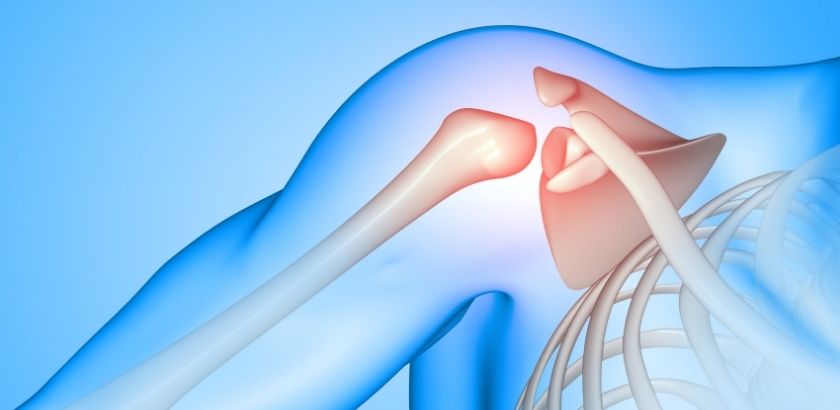

Omuz yaralanmaları, omuz eklemini oluşturan kas, tendon, bağ ve kemik yapılarda meydana gelen hasarlar sonucu ortaya çıkan ortopedik sorunlardır. Omuz eklemi vücudun en hareketli eklemlerinden biri olduğu için günlük yaşamda ve spor aktivitelerinde oldukça aktif şekilde kullanılır. Bu geniş hareket kabiliyeti ise omuz bölgesini yaralanmalara karşı daha hassas hale getirebilir.

Omuz yaralanmaları; spor yaparken, ağır kaldırma sırasında, ani hareketler sonucunda veya düşme gibi travmalar sonrasında gelişebilir. Bazı durumlarda ise tekrarlayan hareketler veya uzun süreli zorlanmalar nedeniyle zamanla ortaya çıkabilir.

Sık görülen omuz yaralanmaları arasında rotator manşet yırtıkları, omuz çıkıkları, tendon iltihapları ve bağ yaralanmaları yer alır. Ayrıca uzun süre bilgisayar başında çalışma, tekrarlayan kol hareketleri veya yanlış spor teknikleri de omuz bölgesinde zorlanmaya ve zamanla yaralanmalara yol açabilir.